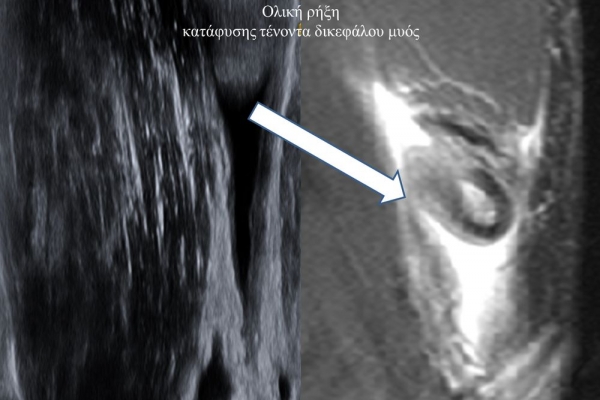

Είναι μια νέα μέθοδος που χρησιμοποιεί υψηλής ευκρίνειας υπερήχους για τη διάγνωση μυοσκελετικών παθήσεων που αφορούν τένοντες, μυς, συνδέσμους, νεύρα και περιφερικές αρθρώσεις. Η μέθοδος αναπτύχθηκε τα τελευταία χρόνια και αποτελεί αναπόσπαστο μέρος στη διαφορική διάγνωση παθήσεων που αφορούν τηνορθοπαιδική, αθλητιατρική, ρευματολογία και παιδιατρική.

Πρόκειται για υπερηχογράφημα υψηλής ευκρίνειας που επιτρέπει την λεπτομερέστατη απεικόνιση (σε επίπεδο χιλιοστού) ακόμη και πολύ μικρών/επιφανειακών ανατομικών δομών και απαιτεί ειδικό υπερηχογραφικό εξοπλισμό καθώς και εξειδίκευση του ακτινολόγου. Η εξέταση γίνεται με δυναμικό τρόπο, δηλ εκτελούνται δοκιμασίες κίνησης του μέλους που πάσχει, ώστε να αποκαλυφθεί η παθολογίαακόμη και όταν δεν είναι εμφανής σε θέση ηρεμίας. Επιπλέον, η εξέταση είναι ανώδυνη και ασφαλής και δεν περιλαμβάνει ακτινοβολία (CT), μαγνητικό πεδίο (MRI) ή παραμονή σε κλειστό χώρο και είναι πολύ ανεκτή τόσο σε ενήλικες όσο και σε παιδιά.